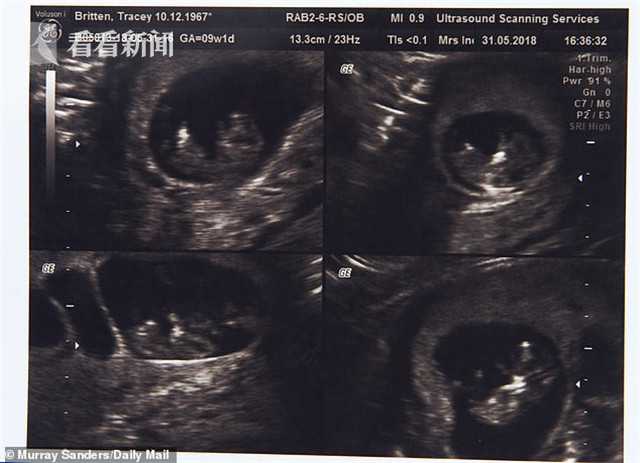

50歲時,特蕾西與丈夫斯蒂芬花了7000英鎊(約合人民幣62317元)在塞浦路斯通過試管嬰兒手術(shù),懷上了四胞胎,其中三個是女孩,一個是男孩,三個女孩中還有一對是同卵雙胞胎。

去年10月,已經(jīng)51歲的特蕾西在倫敦接受剖腹產(chǎn)手術(shù),成功生下四胞胎。四個孩子在出生后立即被送入了重癥監(jiān)護室,靠插管喂食,但他們身體恢復(fù)得很快。去年12月,特蕾西帶著孩子們回到家中。